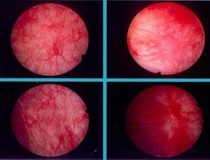

Viêm bàng quang xuất huyết sẽ có biểu hiện là tiểu ra máu, tiểu buốt và bị đi tiểu nhiều lần trong ngày. Xuất huyết bàng quang nếu để kéo dài sẽ gây ra chảy máu nghiêm trọng, cơ thể thường...